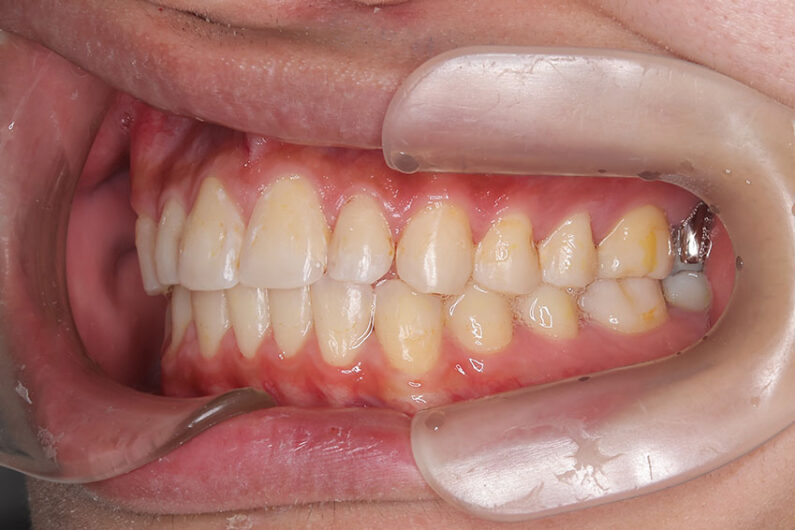

受け口を気にされ、他院からの紹介で来院された患者さんです。

小学2年生、生え変わりの時期から小児矯正を開始しました。

小児矯正で前歯の咬み合わせを改善し、

永久歯列完成後の中学生から非抜歯治療にて本格矯正を開始。

配列し仕上げました。